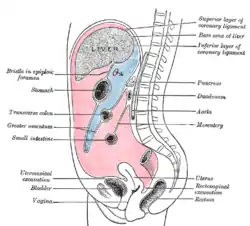

The epiploic foramen, greater sac or general cavity (red) and lesser sac, or omental bursa (blue).

The epiploic foramen, greater sac or general cavity (red) and lesser sac, or omental bursa (blue). Illu female pelvis